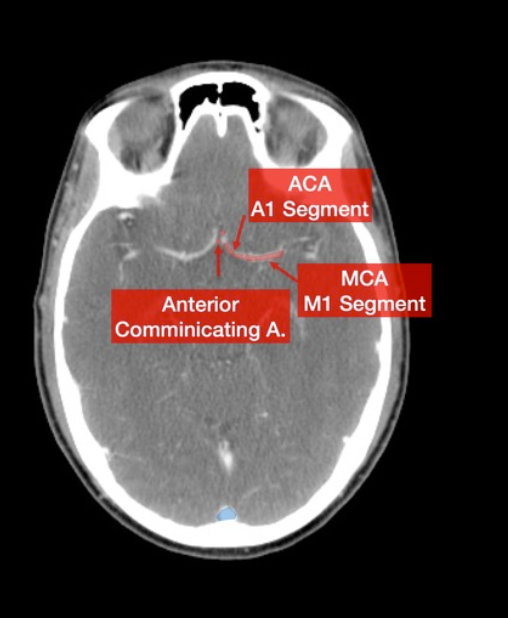

What arteries are these?

Please label the following arteries